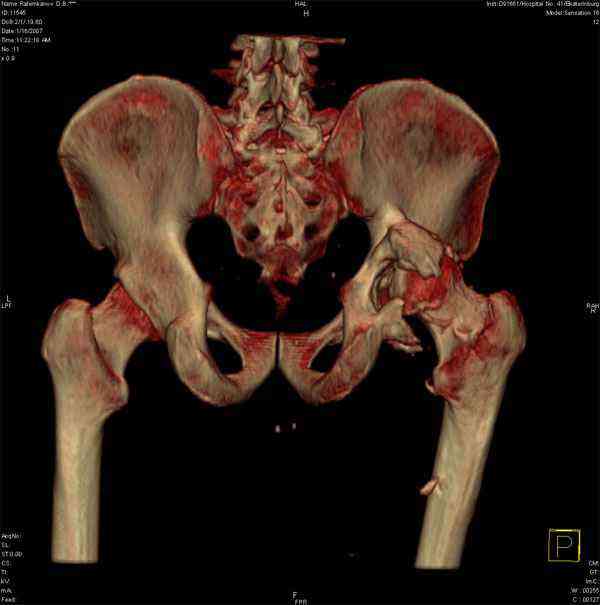

Застарелый вывих бедра

К нам обратился житель Казахстана с застарелым вывихом бедра.

Травма год назад, вместо синтеза заднего края казахскими умельцами установлена клинковая пластина, через 6 мес удалена. Больной ходит с тростью,сгибание в т-б 90, разгибание 170, укорочение 5 см, боли не выражены, анальгетиками не пользуется. Настроен на эндопротезирование в клинике, где есть опыт подобных операций (возможно за рубежом). Наш план: аппарат таз-бедро, постепенное низведение бедра, "октопус" с пластикой. Но с такими большими дефектами мы не сталкивались. Есть вариант сначала аппарат, затем реконструкция впадины, протез обычный через 4-6 мес. Есть мнение не восстанавливать длину. Будем признательны за полезные советы. Было бы интересно посмотреть пример.